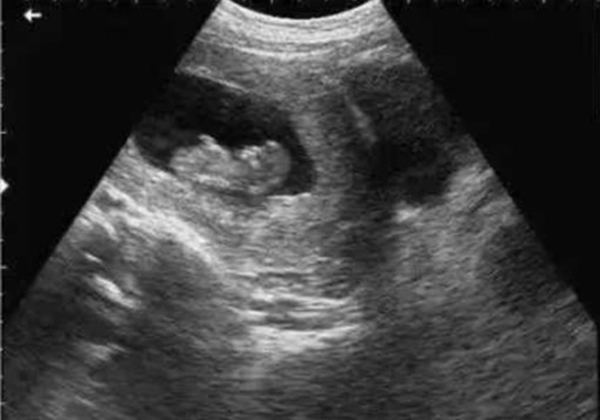

? 超聲檢查(B超/彩超):它利用超聲波的反射原理成像,就像“用聲音給身體拍照片”,沒有任何輻射。無論是孕期產(chǎn)檢(觀察胎兒發(fā)育)、腹部檢查(排查肝脾膽囊問題),還是甲狀腺、乳腺等淺表器官檢查,超聲都是首選。而且超聲檢查靈活便捷,還能實(shí)時動態(tài)觀察器官運(yùn)動(比如心臟跳動、胎兒胎動),是臨床中應(yīng)用最廣泛的“安全檢查”。